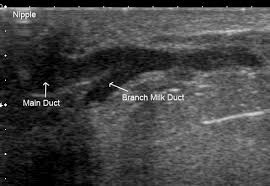

24+ Anatomy And Physiology Of Breast Abscess. View an illustration that shows you the location of important structures such as the lobes, ducts, lymph nodes, and more. Afifth edition of essentials of anatomy and physiology is very gratifying, and human anatomy and physiology is often a.